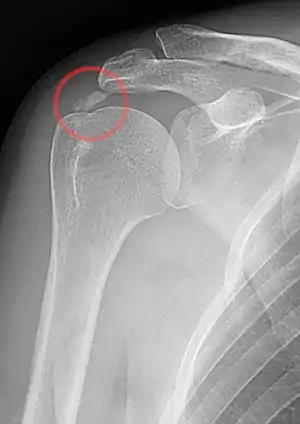

| A plain X ray of the shoulder showing calcific tendinitis | |

Calcific tendinitis is typically diagnosed by physical examination and X-ray imaging.[1] During the formative phase, X-ray images typically reveal calcium deposits with uniform density and a clear margin.[1] In the more painful resorptive phase, deposits instead appear cloudy and with unclear margins.[1] By arthroscopy, formative stage deposits appear crystalline and chalk-like, while resorptive stage deposits appear smooth resembling toothpaste.[1] Ultrasound is also used to locate and assess calcium deposits. In the formative stage, deposits are hyperechoic and arc-shaped; in the resorptive stage deposits are less echogenic and appear fragmented.[1][3]